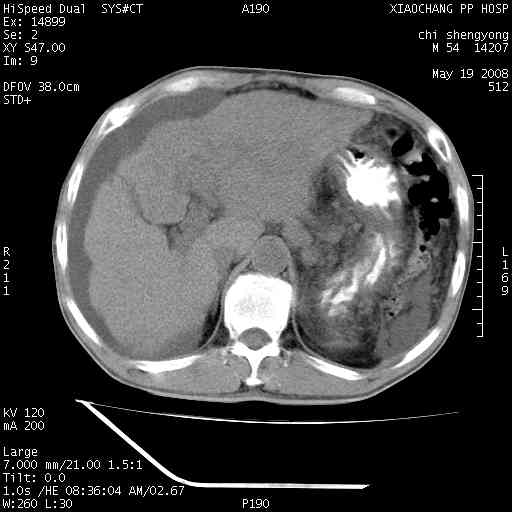

以下是引用zjzjr在2008-5-21 10:52:00的发言:[br]肝左叶巨块型肝癌伴门静脉左支瘤栓形成.肝硬化、腹水,胃底静脉曲张,脾术后改变。

以下是引用随光逐影在2008-5-21 16:20:00的发言:[br]1)肝左叶肝癌伴门静脉左支瘤栓形成,腹膜后淋巴结转移。2)肝硬化、腹水、胃底静脉曲张。3)胆囊炎。4)脾脏缺如,为切除术后所致。